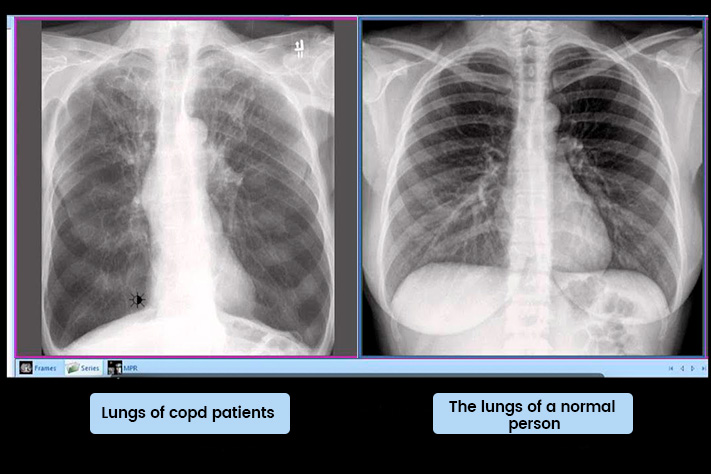

"Because most doctors don't know to look for it. We can't see it on X-rays. We keep prescribing treatments that only work on the surface."